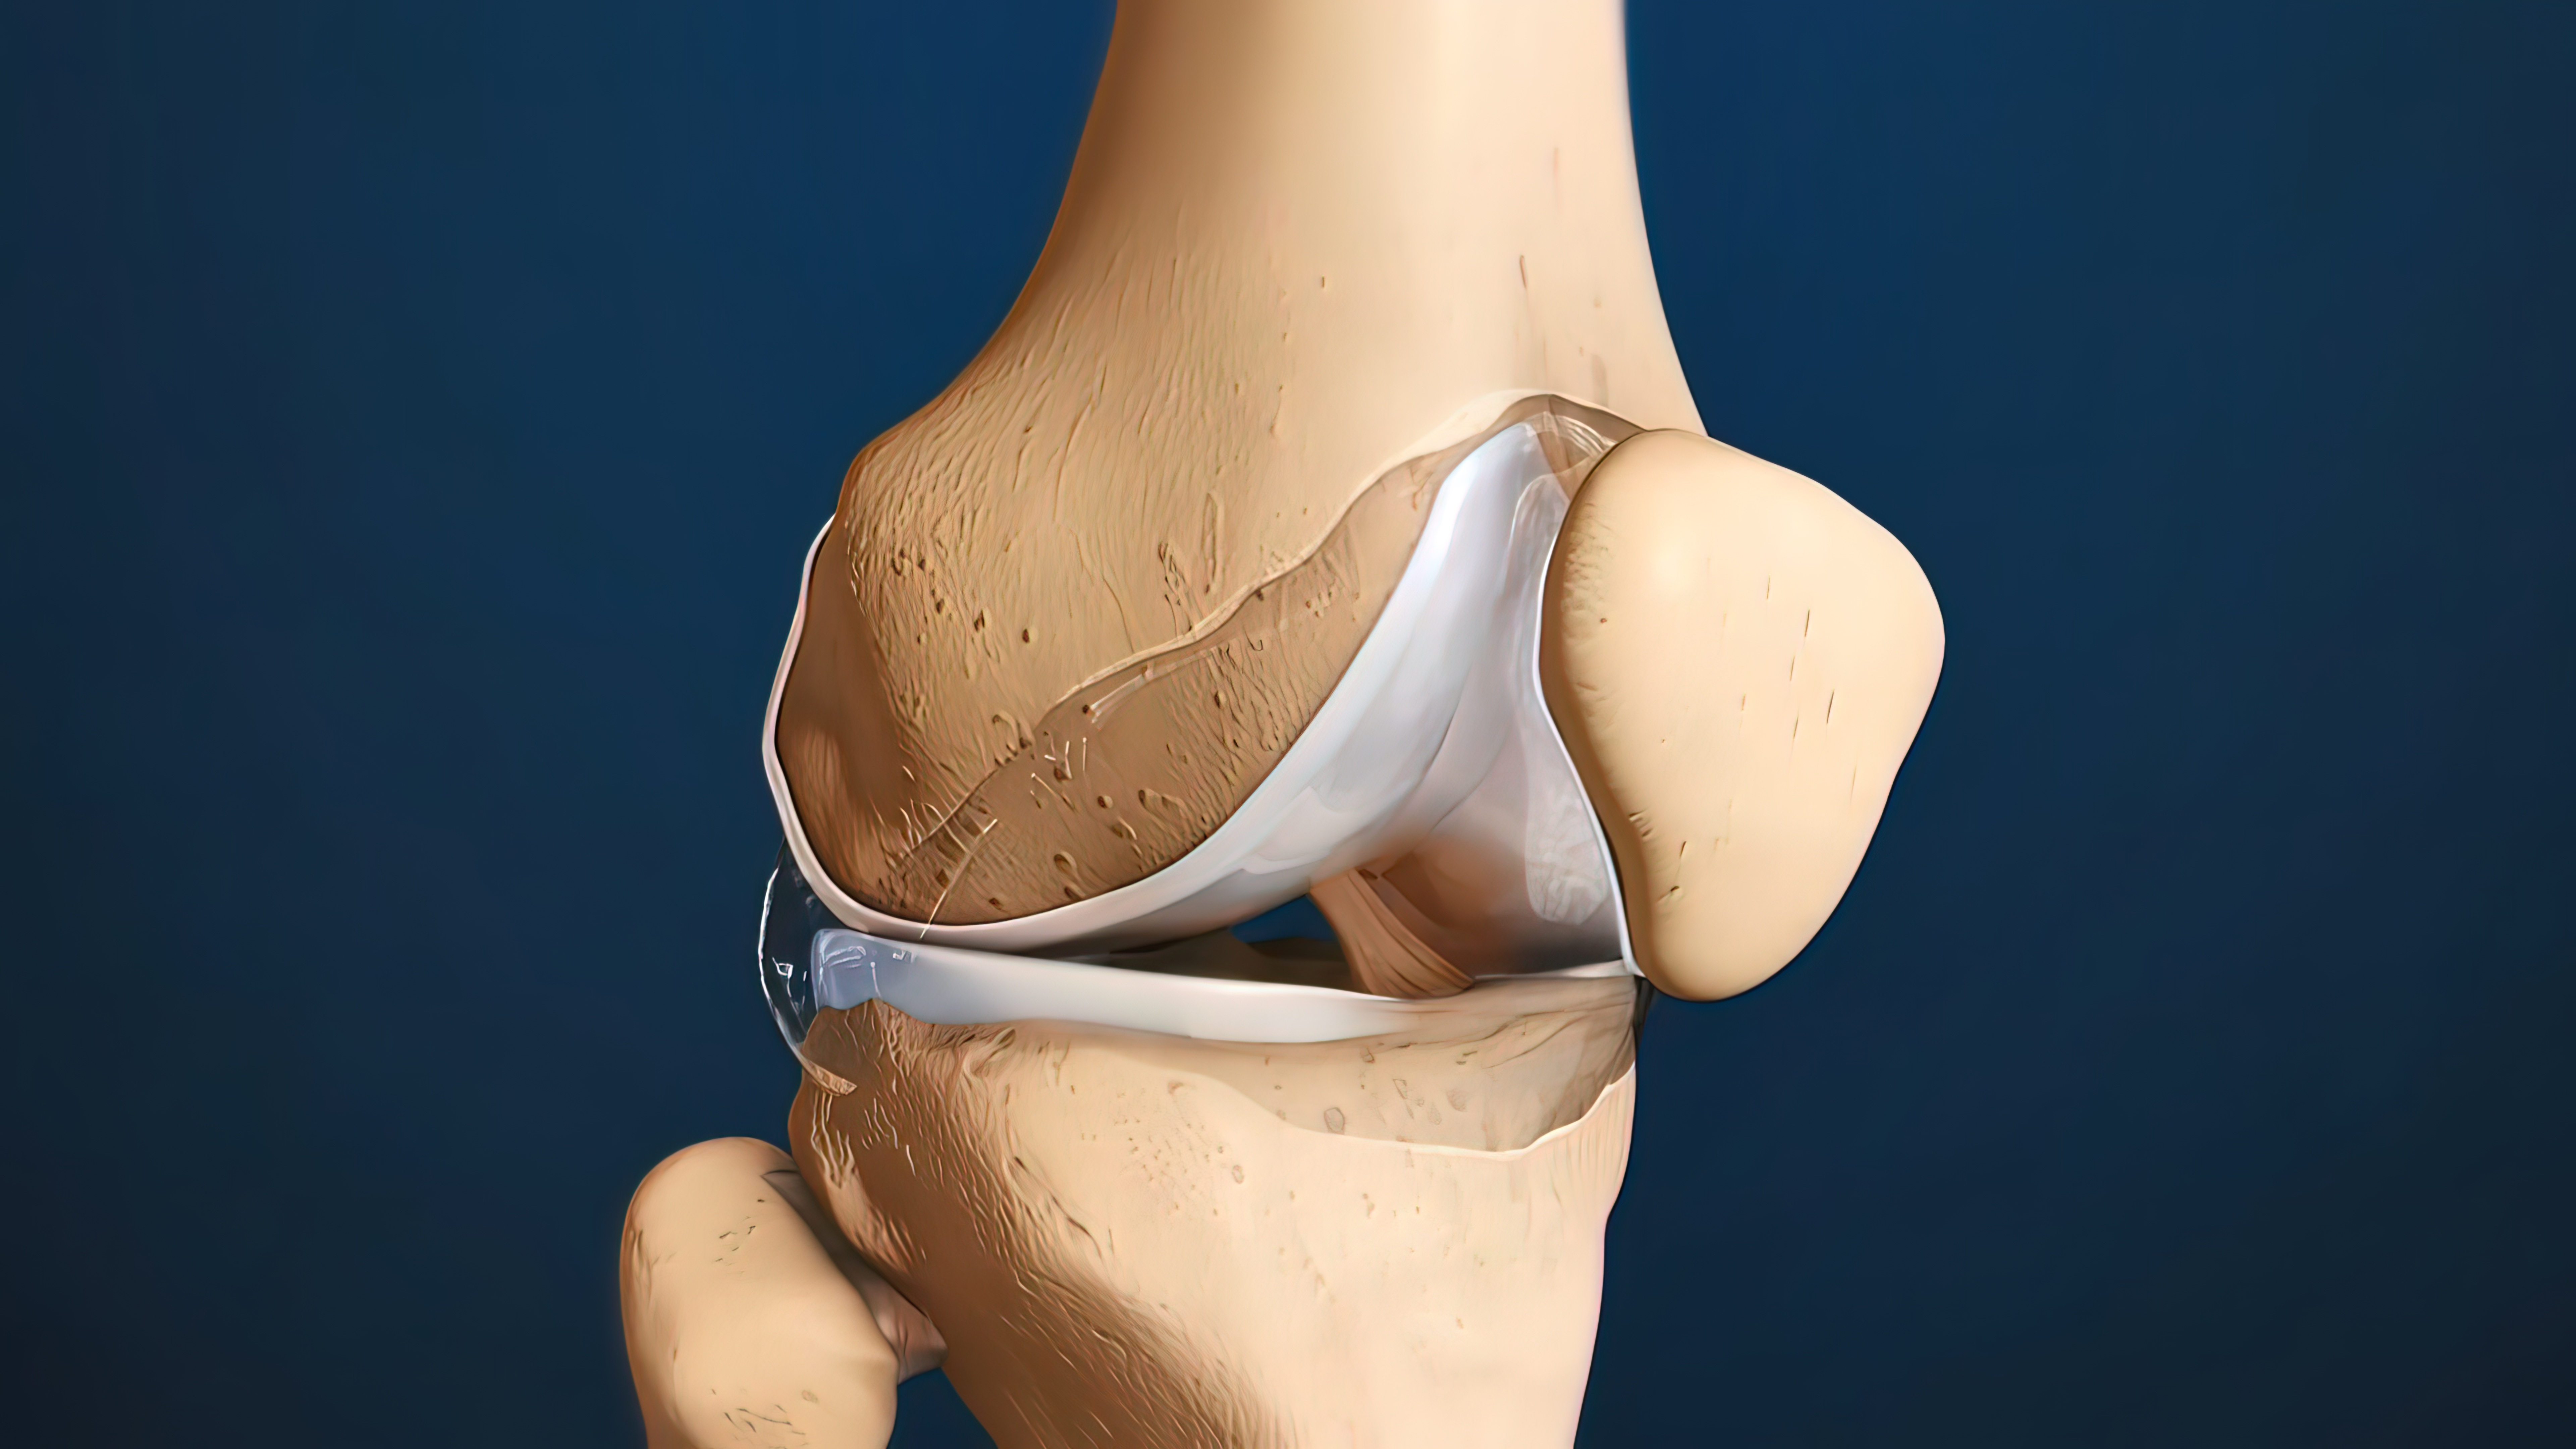

膝关节置换术后早期与晚期失败案例!